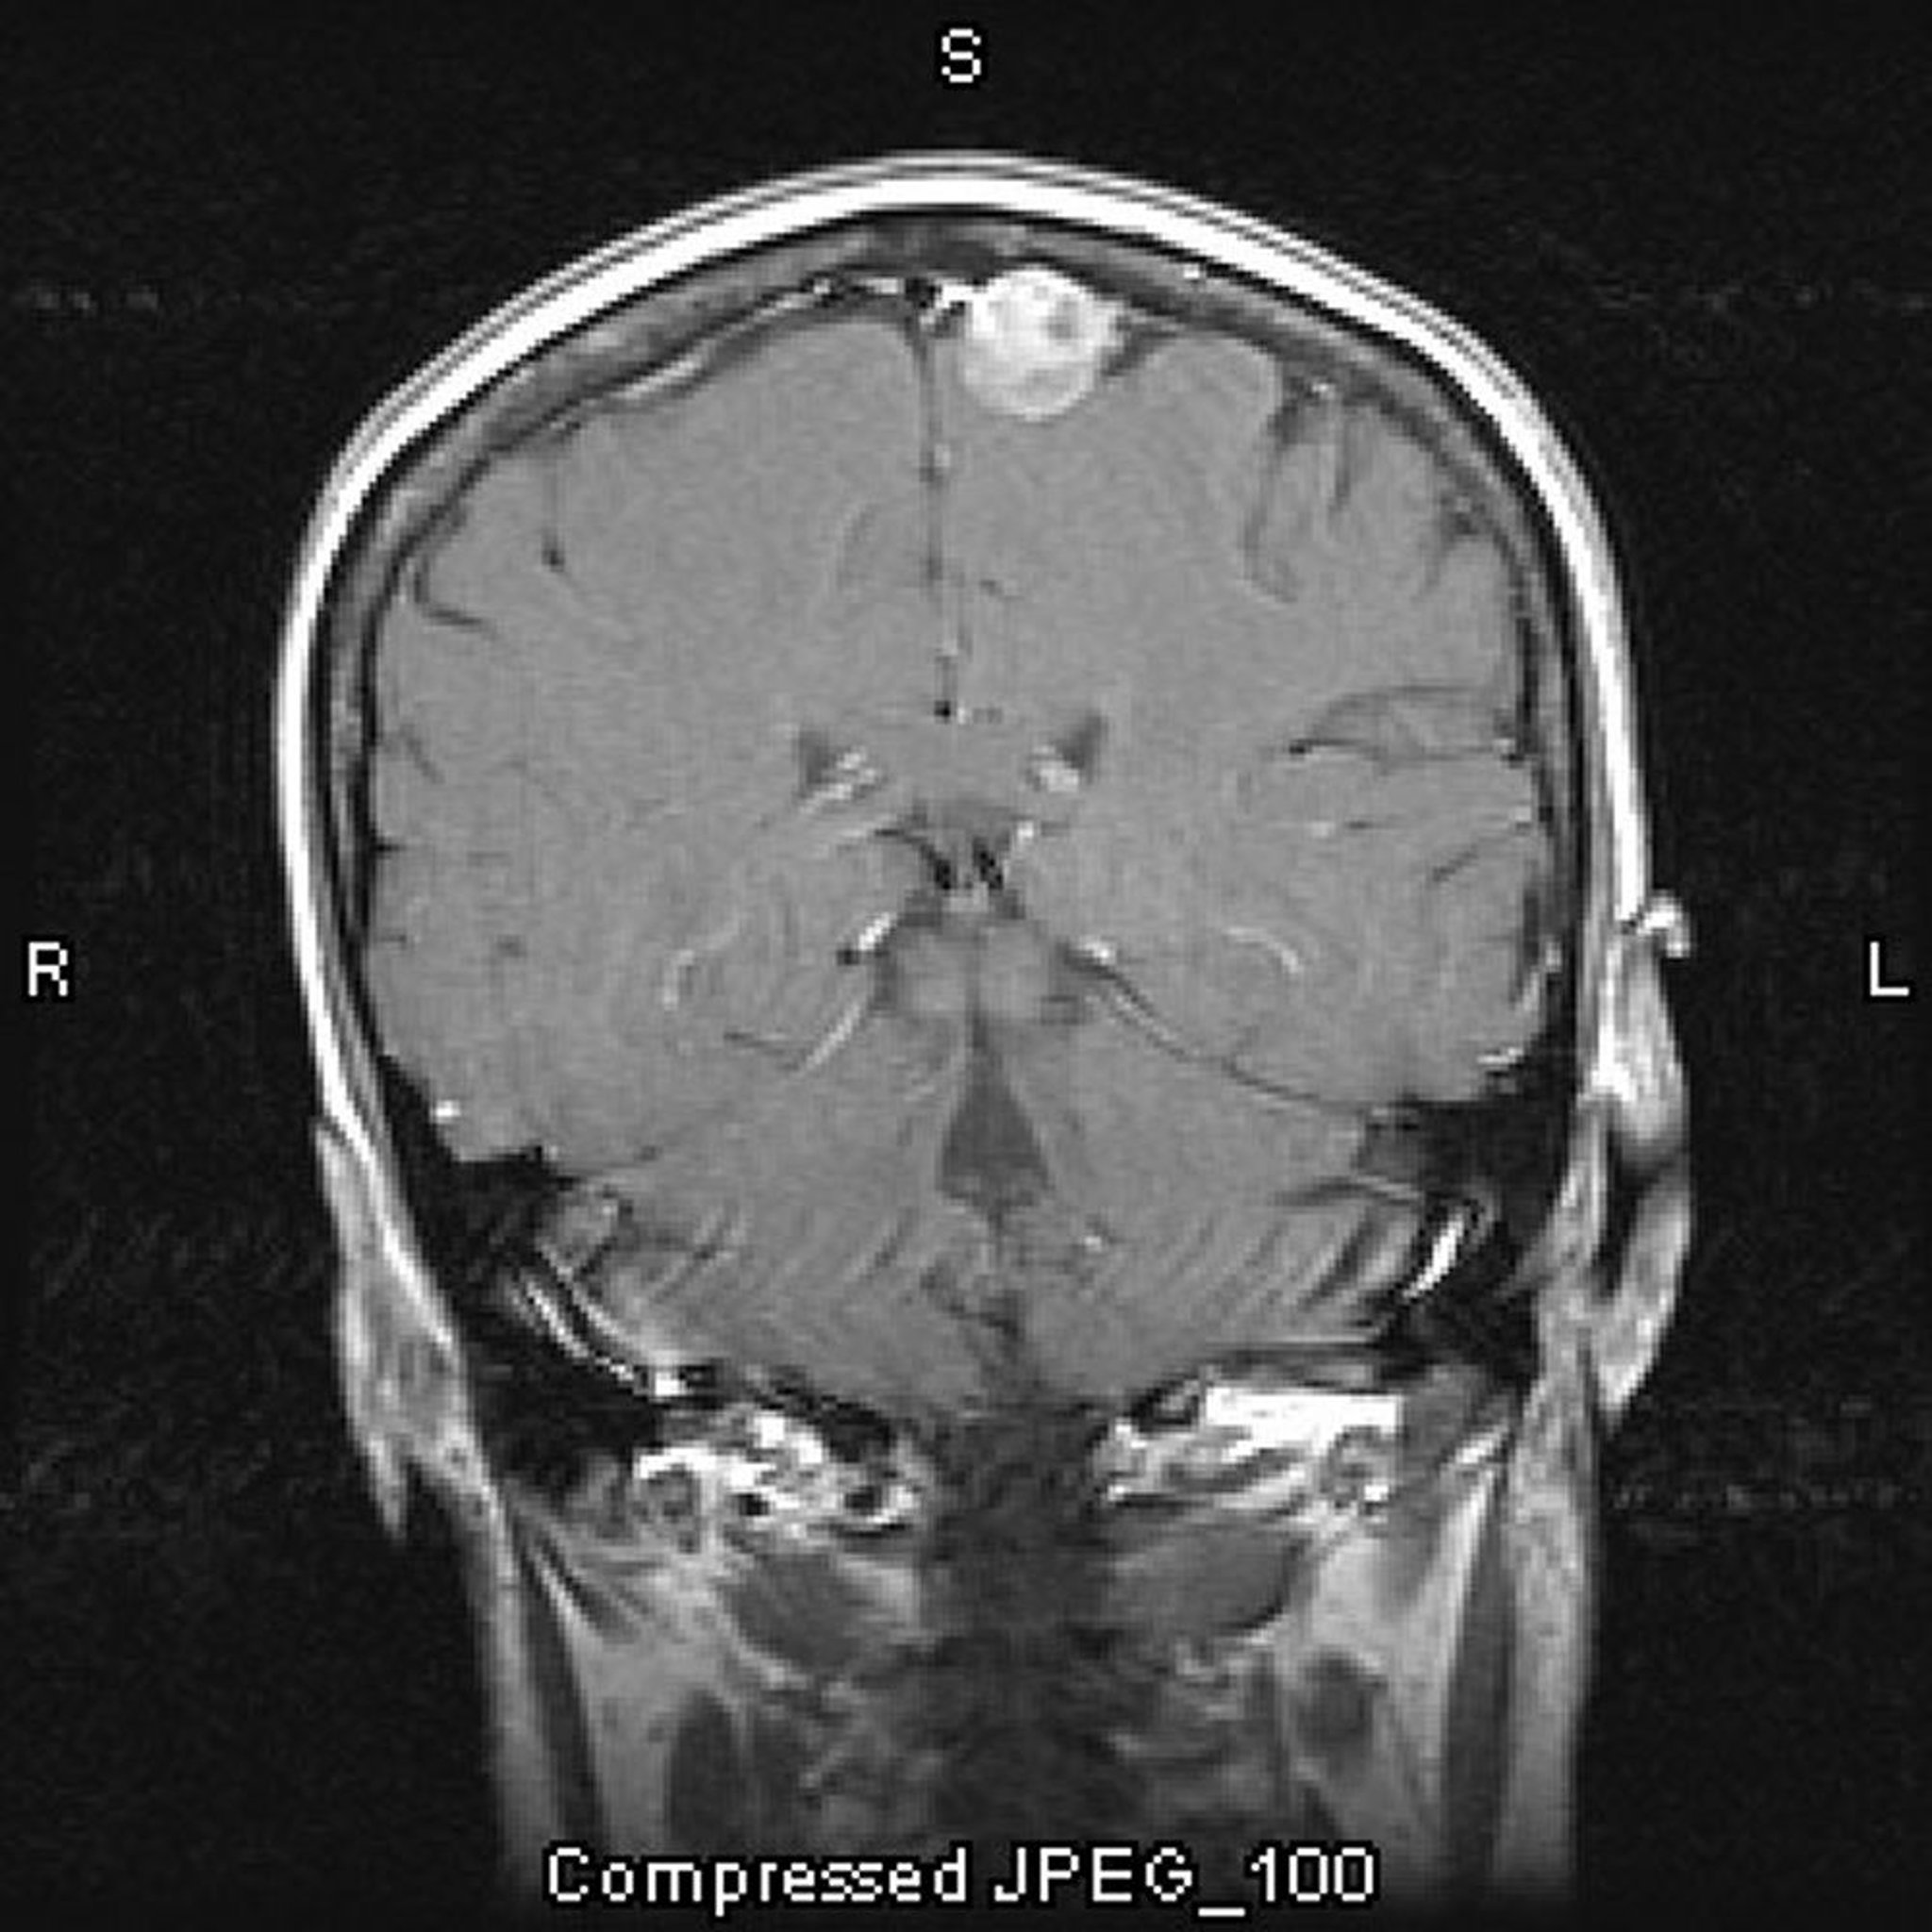

Meningeom, parasagittal

Diese kontrastverstärkte MRT-Aufnahme zeigt ein Meningeom. Die parasagittale Lokalisation ist typisch für Meningeome.

Image courtesy of William R. Shapiro, MD.